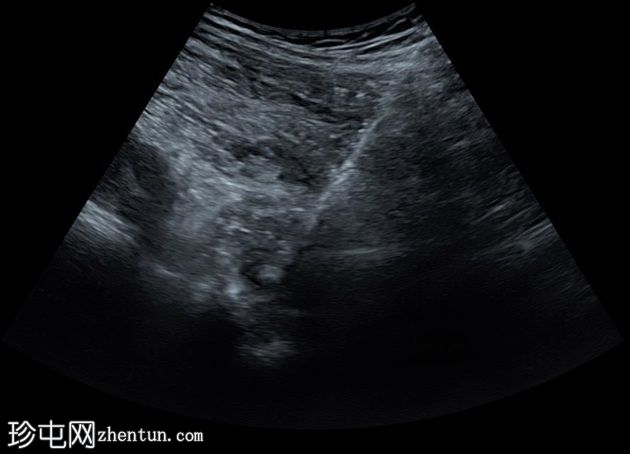

超声

检查

矢状位

在超声引导下,对位于左侧大腿内侧上部的膨胀性溶骨性破坏性肿块进行了穿刺活检。